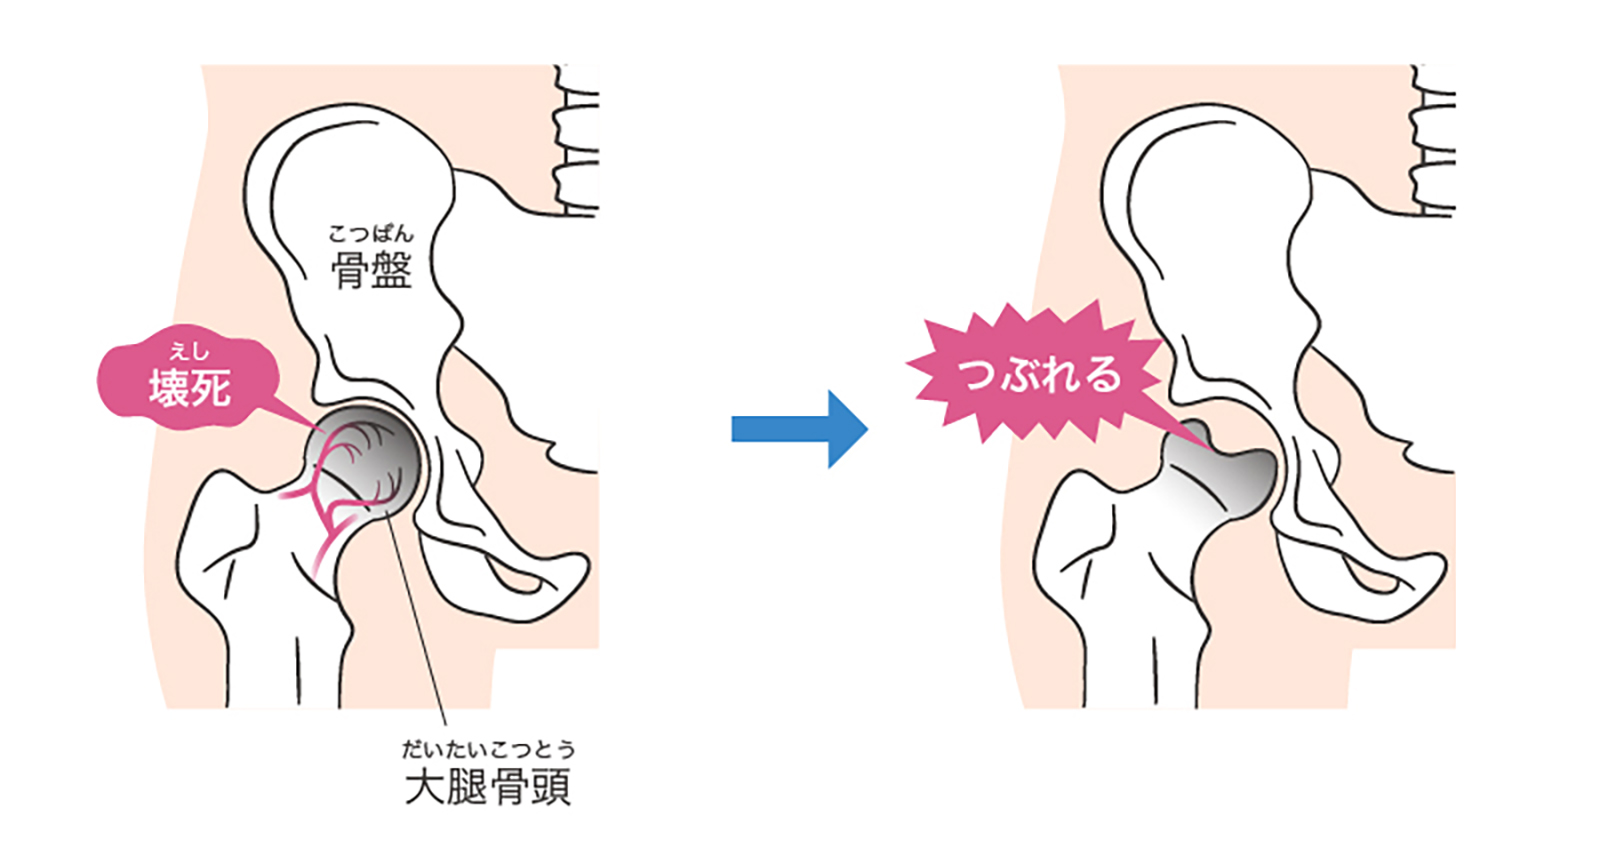

大腿骨頭壊死症

だいたいこっとうえししょう

股関節の骨に血流が届かなくなり、骨の一部が壊れてしまう病気です。進行すると骨がつぶれ、強い痛みや可動域の制限が出ます。原因不明なこともありますが、ステロイド薬や多量の飲酒が関係することもあります。